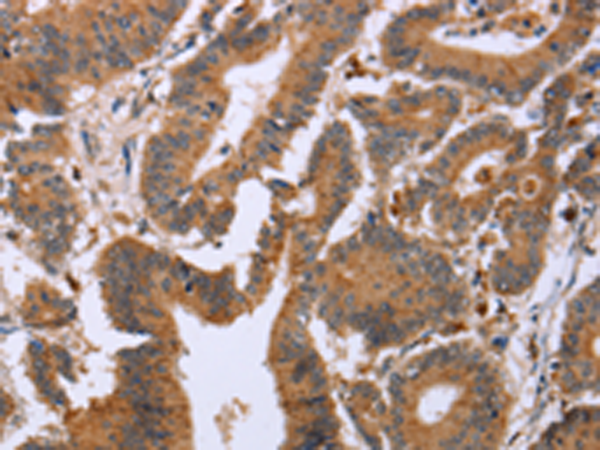

分类: 科研抗体货号: P08287别名: EPDR; UCC1; MERP1; MERP-1应用: WB,IHC反应种属: Human, Mouse, Rat